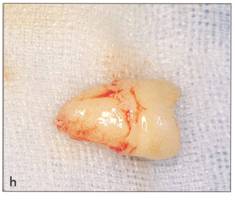

Fi 545e45f g 5-2h Extracted donor tooth. This tooth seems to be at developmental stage 6. |